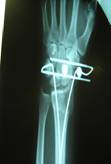

Come le fedelissime già sanno, il mese scorso sono inciampata in un tappeto e mi sono fratturata il polso:frattura scomposta del radio e ulna.

Accorsi i figli mi hanno portata al Policlinico Gemelli: arrivata alle 16,30 e a ..mezzanotte ero a casa! con un mezzo gesso e la diagnosi della frattura(naturalmente scomposta, vi risparmio la descrizione della manovra dell’ortopedico per la riduzione ..) poi mi hanno comunicato che potevo scegliere tra un gesso per 45 giorni che mi avrebbe immobilizzato fino alla spalla, con successiva lunga e dolorosa riabilitazione, o l’introduzione di fili e ferri a tenere assieme i ..pezzi, con un decorso di 35 giorni ,una semplice fasciatura morbida del polso, e la possibilità di muovere e utilizzare la mano..ça va sans dire.. ho scelto i ferri..

la tecnica si chiama EPIBLOC:http://www.medicinadellamano.it/epibloc.php

Nel successivo primo pomeriggio sono stata operata, con anestesia del braccio(fastidiosa..) e sedazione..una esperienza bellissima la sedazione, mi pareva che avevo appena cominciato a pensare all’operazione quando mi hanno comunicato che tutto era già stato fatto!!